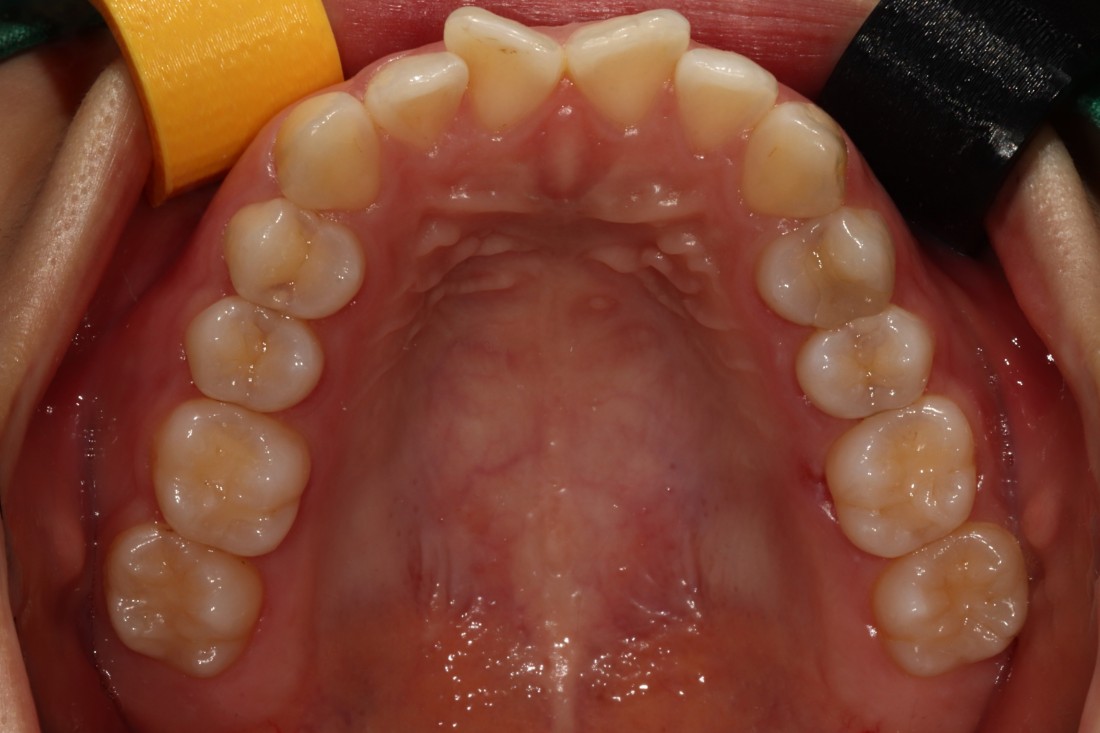

발치교정, 비발치교정을 결정하는 것은

교정 전 3차원 105항목 정밀검사를 통해

교정전문의 대표원장님과의

세심한 상담을 통해 정하게 됩니다.

무조건 비발치 교정만이 좋은 것은 아니며,

개인차에 의해 발치교정이 필요한 경우에는

발치교정을 통해 원하는 교정치료 결과를

얻을 수 있습니다.

광주 교정치과는

200케이스 넘는 교정사례를

상세하게 공유해드리고 있기 때문에

실력을 믿고 맡기셔도 좋습니다.

더 다양한 교정 전/후 사례는

위의 사진을 클릭하시면

확인하실 수 있습니다.